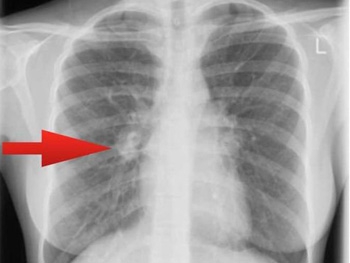

Запорожская область занимает лидирующую позицию в антирейтинге заболеваемости туберкулезом - на 100 тысяч 57 заболевших. А в нашем городе статистика еще хуже - на 100 тысяч населения Мелитополя 87 человек больны различными формами туберкулеза.

Поэтому в Мелитопольском горздравотделе напоминают о необходимости ежегодно делать флюорографию. Тем более, что анализ этот бесплатный.

Напомним, туберкулез - инфекционное заболевание, поражающее легкие, а также кости, суставы, кишечник.